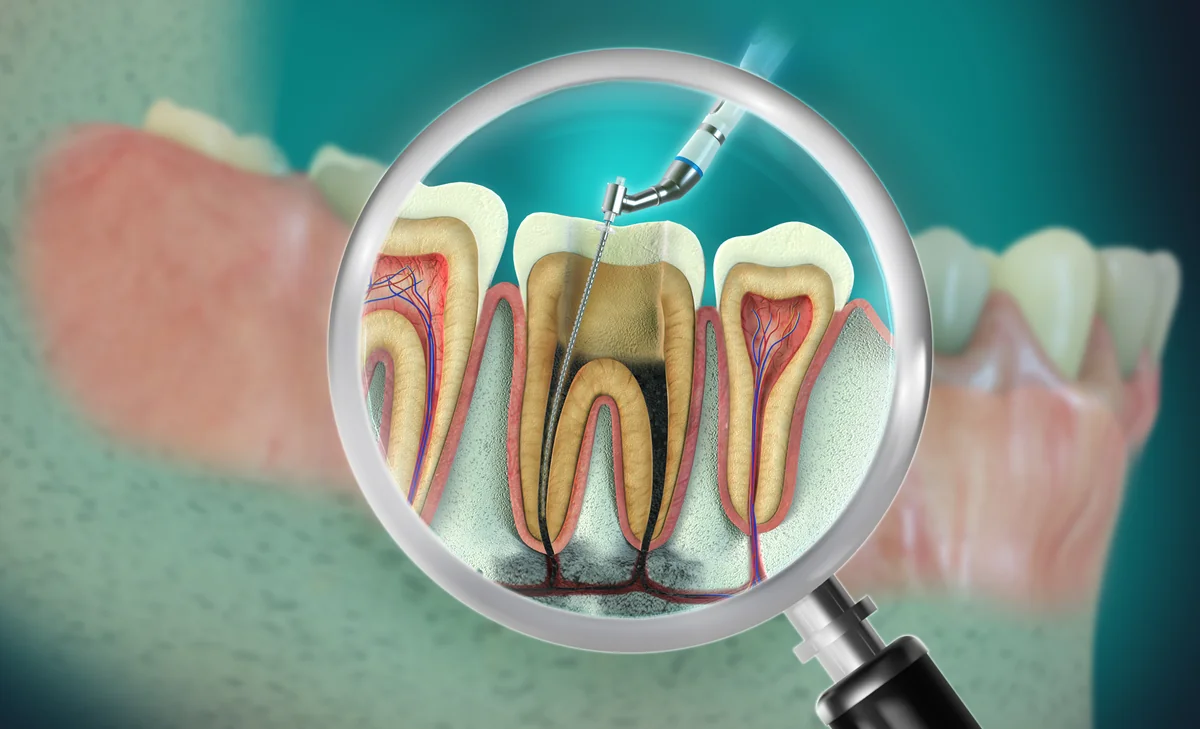

Endodonție

Tratamente de canal realizate cu rigurozitate pentru salvarea dinților afectați și eliminarea disconfortului.